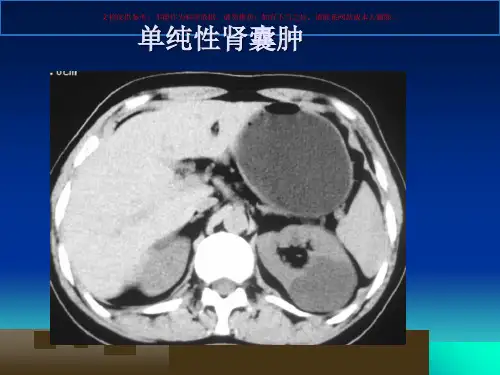

单纯性肾囊肿